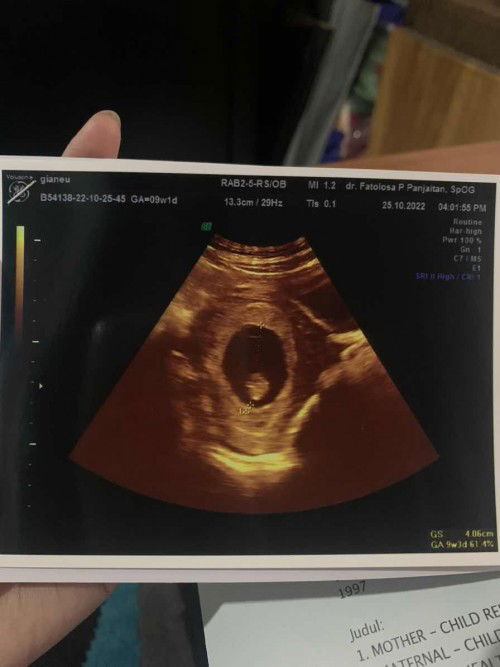

usg 9 minggu

bund mau tanyaa kmarin saya baru usg kandungan 9 minggu, ini hasilnya terus dokter bilang ini masih kantung rahim, apakah kandungan termasuk sehatt ya? atau emang usg 9 minggu emang baru seperti ini?